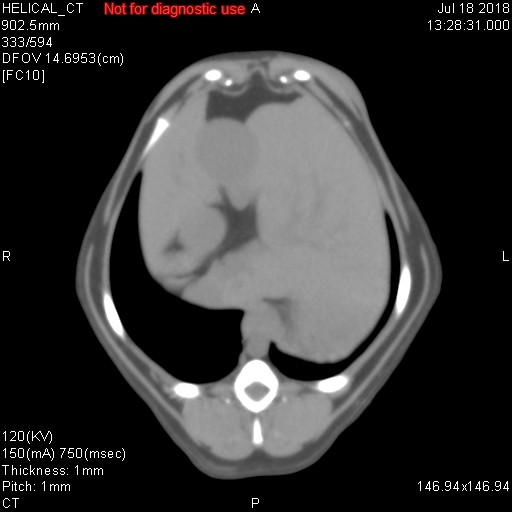

上記に載せました各写真ですが、CT検査で様々な条件で撮影した同一臓器(肝臓/胆嚢/胃/十二指腸/門脈/後大静脈/大動脈/肝動脈)です。CT検査では、そのまま撮影するプレーン、造影剤を使用する動脈相・門脈相・平行相がありますが、上記写真がどれかわかりますでしょうか??

シンプルに、一番上がプレーンです。臓器のシルエットくらいしかわかりません。その次が動脈相で、中央にピョろっとある肝動脈や背骨側にある太い血管(大動脈)が白くはっきりと写ります。また薄っすらと肝臓内にも多くの動脈がありますので、チラチラと動脈だけが見えてきます。3番目が門脈相といって肝臓の外にある門脈が白く際立ち、さらには肝臓内にある門脈(門脈枝)まで白くキレイに写ってきます。そして最後が平行相ですが、これは造影剤が通過して結構時間が経過した際の写真ですが、例えば具合が悪い臓器だと造影剤が抜けきるのが遅いため、時間が経過しているにもかかわらず造影剤がまだ残ってしまったりしますので、そのような際の評価に活かされます(あと悪性腫瘍など癌なども同じような見え方をします)。

造影剤を投与したあと20秒経過したときに撮影するのが動脈相、40秒が門脈相、120秒が平衡相といい、時間経過でCTスキャンを行って、様々な条件のもとで画像は分析されていきます。あと細かいですが、とある数字を設定して、その数字に達したらCTスキャンが開始されるなど、撮影方法にもいろいろあります。ただ単純にCTスキャンをしているだけではなく、造影剤を使用したり、投与時間を細かく設定したり、さらにいろいろな条件下で画像を比較して、最適かつ確実な画像診断を行っているのが、CT検査なのです。